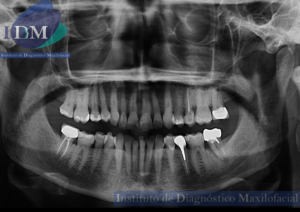

Caso 300 – IDM – HIPERPLASIA DE APÓFISIS CORONOIDES DE LADO DERECHO – IDM

Paciente femenino de 16 años acude al Instituto de Diagnóstico Maxilofacial (sede Miraflores) para evaluación quirúrgica. Radiografia Panorámica A la evaluación de la radiografía panorámica